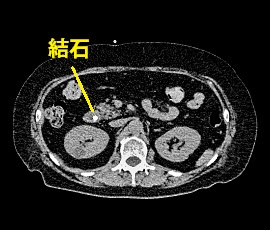

急性腹症にて救急受診。精査の結果、総胆管結石と診断。腹腔鏡下胆管切開結石除去術(胆嚢摘出術含む)を施行した。

CT画像